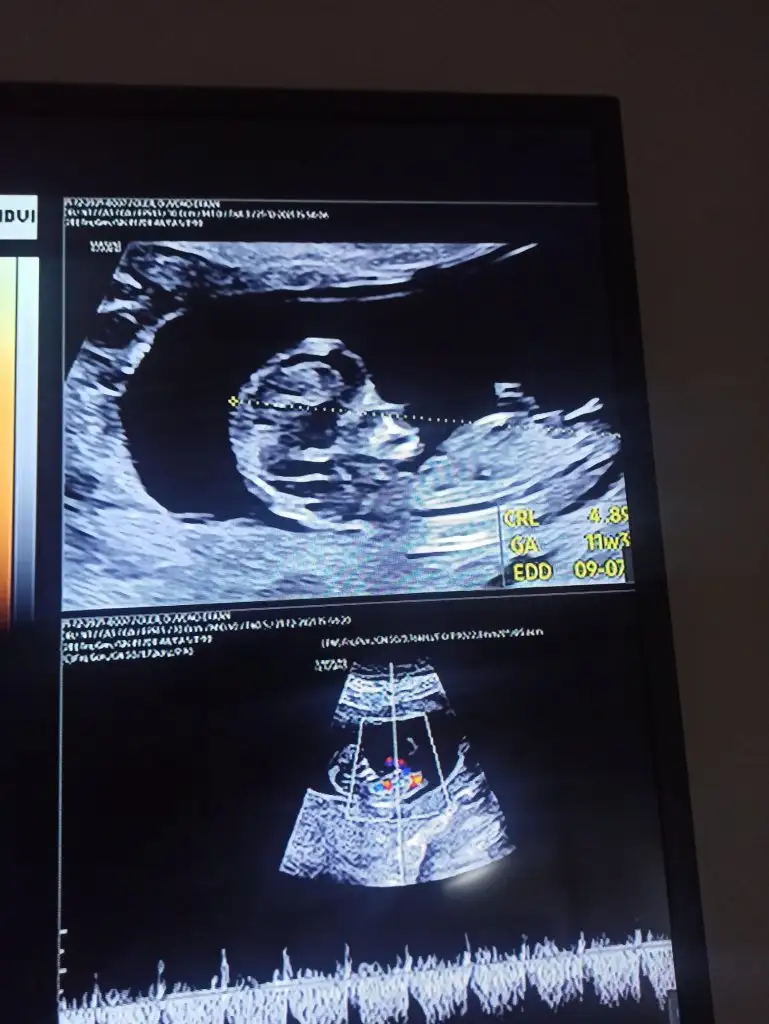

11+0 günlük. cinsiyet tahmininiz var mı acaba?

• WhatsApp Image 2021-12-22 at 11.31.30.webp

44,5 KB · Görüntüleme: 83